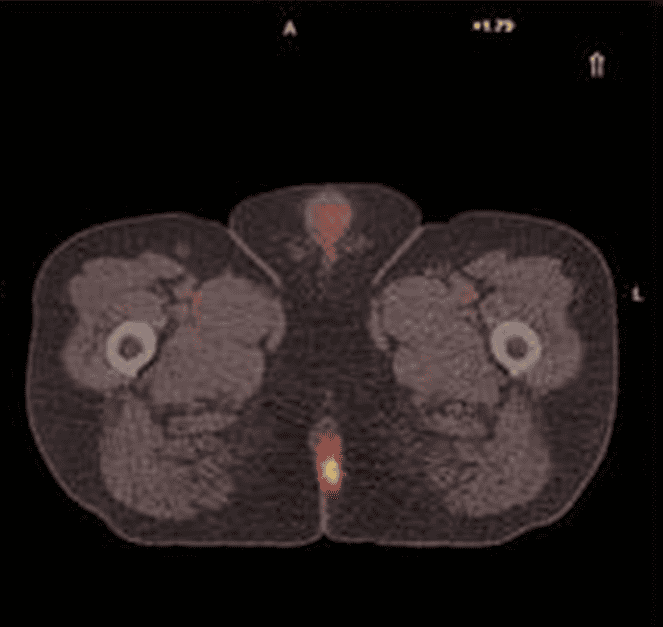

Anal sphincter preservation with chemoradiotherapy is standard treatment for most patients with anal cancer, but anal cancer remains challenging to treat and imaging plays a vital role for treatment planning. This course comprises of three tutorials where we discuss anal anatomy, tumour localisation and staging, patterns of uptake on FDG PET-CT, radiotherapy planning, and patient management, as well as, the challenging role of PET-CT imaging for response assessment.

- Describe patterns of uptake on FDG PET-CT imaging